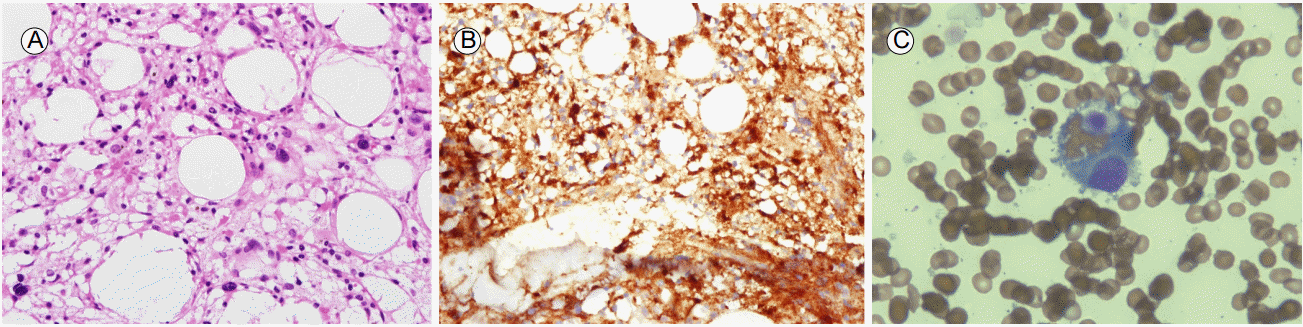

Figure 1.

Microscopic analysis of a bone marrow biopsy specimen showed hypercellular marrow for the age of the patient (cellularity; 50%) (A). CD68 staining revealed markedly increased histiocytic infiltration (B). A bone marrow aspiration specimen showed histiocytic cells with phagocytosed lymphocytes and erythroblasts (C). (A: hematoxylin & eosin stain, ×400, B: CD68 immunostain, ×400, C: oil-immersion field, Wright-Giemsa stain, ×1000)